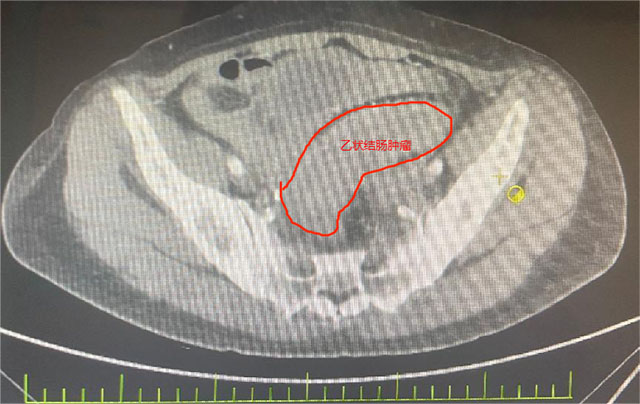

她被确诊为乙状结肠癌,肿瘤已“疯狂”侵犯膀胱、子宫、输尿管等多个盆腔脏器,还伴随不全性肠梗阻。2个月前在外院住院治疗,因手术风险大,外院仅为她做了横结肠造口术缓解梗阻,可术后不幸出现结肠膀胱瘘——小便中混着大便的症状让她痛苦不堪,叠加尿路感染、肿瘤引发的消化道出血,以及尿路梗阻导致的肾功能不全,多重并发症叠加,生活质量跌至谷底。

先是完整切除受肿瘤侵犯的直肠与乙状结肠原发灶,紧接着剥离与肿瘤紧密粘连的子宫及双侧附件并完整移除,随后小心翼翼分离膀胱与周围组织,将受侵膀胱全部切除——前三项切除手术已耗极大精力,团队仍需在腹腔镜下用回肠精心构建新的膀胱通路,确保患者术后排尿功能正常。